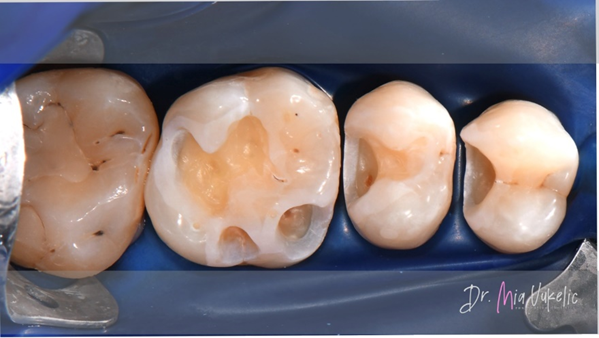

The patient visited the clinic for an annual check-up. Following a clinical and radiographic examination, a secondary carious lesion was diagnosed on occlusal surface of tooth 26 and two additional carious lesions on the distal surfaces of teeth 24 and 25. The patient reported no specific symptoms. The prescribed treatment involves the placement of a Class I restoration on tooth 26 and Class II restorations on teeth 24 and 25.

After proper isolation with a rubber dam and placement of wedges, the cavity preparation began with a cylindrical bur. Following the removal of the restoration, we proceed to eliminate demineralized dentin using a steel bur. The final cavity refinement involved converting convergent walls into divergent ones and polishing the internal cavity surface with diamond polishing burs.